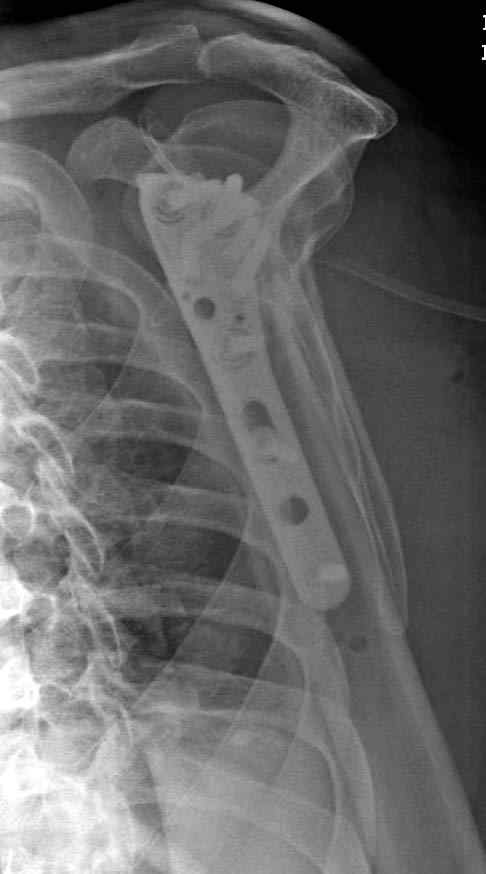

Здесь пример открытой репозиции 57 летнего с переломом плеча (1,2) смещение обнаружено на интероперационном снимке. При нормальной прямой проекция (3) угловое смещение обнаружили в аксиальной проекции (4)

После устранения смещения пластина установлена выше (5,6,7) и финальные снимки (8,9,10)

Подбор импланта тоже имеет значение, например многие импланты направлены для фиксации перелома без учета ротаторной манжетки. Предпочтительными являются низко сидящие полиаксиальные пластины, где верхние шурупы можно проводить под углом в 120 градусов. (11)

Пластина от Synthes или ее копии (надеюсь простят критику друзья из Деоста) считаются трудным из-за обширности доступа, особенно при установке верхне-заднего шурупа, где доступ надо расширять в верхнем отделе до ротаторной манжетки. Верхне сидящие импланты предназначены для проведения опоры (buttress) за бугристость плеча, но тогда приходится сталкиваться с подакромиальным импинжментом.

дополнительные снимки по протезированию